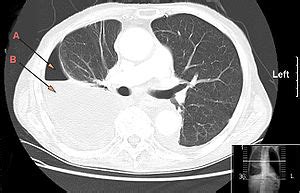

Loculated Pleural Effusion Ct Scan / Empyema and Thoracoscopic Surgery, Mumbai, India / Pleural fluid is seen extending to the right oblique fissure.

Ideal for localizing, loculated or small effusions for thoracentesis. Ct scan of the chest. The largest pocket of fluid is present posteriorly at the right lung base, with associated atelectasis and minor consolidation. Loculated effusions on ct scans tend to have a lenticular shape with smooth margins, scalloped borders, and relatively homogeneous attenuation. We analyzed ct and sonographic scans of 31 patients with loculated pleural effusion treated with intracavitary urokinase. Ct scan of the chest. We develop an automated method to evaluate pleural effusion on ct scans, the measurement of which is prohibitively time consuming when performed manually. Loculated pleural effusions may be treated by thoracentesis, thoracoscopy, thoracostomy tube drainage, open drainage, or thoracotomy and decortication. Causes of pleural effusion that can be effectively treated or controlled include an infection due to a virus, pneumonia or heart failure. Courtesy of charlie strange, md. Medially situated fluid collections adjacent to the mediastinum are easily delineated on ct scan. Nodular thickening of the pleura suggests pleural metastasis. Axial contrastenhanced ct scan showing moderate left pleural effusion as loculated collection with thickening of pleura (arrows) in a case of mesothelioma open in a separate window figure 14 (a, b)

The largest pocket of fluid is present posteriorly at the right lung base, with associated atelectasis and minor consolidation. This can be done at the bedside. Pleural tumors, cysts, and loculated effusions all appear homogeneous on chest radiographs, but should be distinguished with ultrasound, ct, or magnetic resonance imaging (mri) scanning. Loculated effusion chest ct scan. We analyzed ct and sonographic scans of 31 patients with loculated pleural effusion treated with intracavitary urokinase. The patient was diagnosed with pneumonia with a loculated parapneumonic effusion. Pleural fluid may loculate within the fissures, particularly in heart failure, and manifest as vanishing or phantom tumors (pseudotumors). Ct of the chest showing a loculated pleural effusion (arrows), which is parapneumonic in origin. Pleural tumors may be regarded as solid, but they are not always entirely homogeneous. Axial contrastenhanced ct scan showing moderate left pleural effusion as loculated collection with thickening of pleura (arrows) in a case of mesothelioma open in a separate window figure 14 (a, b) Pleural effusions are characterized on ct by attenuation values between those of water (0 hounsfield units hu) and soft tissue (approximately 100 hu), typically in the order of 10 to 20 hu. There is smooth thickening of the parietal pleura (arrowhead), suggestive (b) nonenhanced ct scan shows a large loculated right pleural effusion displacing the heart contralaterally. Ct scan of the chest.

Pleural masses may be seen. On ct, 21% of pleural effusions showed loculation. Medially situated fluid collections adjacent to the mediastinum are easily delineated on ct scan. Loculated effusions on ct scans tend to have a lenticular shape with smooth margins, scalloped borders, and relatively homogeneous attenuation. Ideal for localizing, loculated or small effusions for thoracentesis.

Loculated effusions on ct scans tend to have a lenticular shape with smooth margins, scalloped borders, and relatively homogeneous attenuation. Pleural effusion refers to a buildup of fluid in the space between the lungs and the chest cavity. Chest ct scan with intravenous contrast in a patient with mixed. 3 & 4] confirmed the appearance of a complex pleural effusion with associated consolidation of the right hemithorax. Loculated effusion chest ct scan. Pleural fluid may loculate within the fissures, particularly in heart failure, and manifest as vanishing or phantom tumors (pseudotumors). Pleural effusion may extend into the major fissures and give them a characteristic appearance. Pleural effusions are characterized on ct by attenuation values between those of water (0 hounsfield units hu) and soft tissue (approximately 100 hu), typically in the order of 10 to 20 hu. Chest ct revealed a large loculated left pleural effusi. Ideal for localizing, loculated or small effusions for thoracentesis. This can be done at the bedside. Ct of the chest showing a loculated pleural effusion (arrows), which is parapneumonic in origin. Nodular thickening of the pleura suggests pleural metastasis.